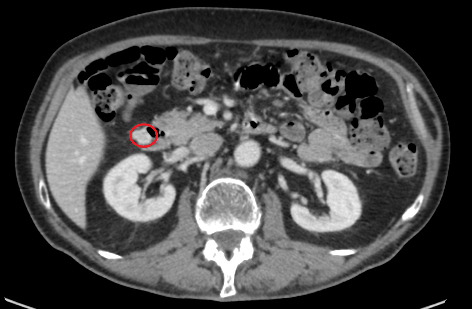

背景:胃肠道间质瘤(gist)是消化道的间质肿瘤,可累及消化道的任何部分。这些肿瘤可能是无害的,也可能危及生命。材料与方法:报告一位外科医生在芬兰桑拿浴室中跌倒,立即感觉肋骨断裂的病例。核磁共振及超音波显示三根肋骨骨折及脾内血肿。增强计算机断层扫描(CT)显示小脾内异常,但没有血肿。顺便说一句,左肾上腺的一个偶然瘤被诊断出来。三个月后,进行对照CT扫描。肾上腺的放射学表现和实验室检查符合良性腺瘤。顺便说一句,诊断出一个小的十二指肠肿瘤。同时出现贫血(血红蛋白:104 g/L)和缺铁(铁蛋白:8 g/L)。食管胃十二指肠镜检查显示肿瘤位于球降连接处后。由于肿瘤位于粘膜下,病理诊断失败。三个月后,行根治性手术切除肿瘤,切除边缘为2mm,并初步关闭十二指肠。病理检查显示黏膜下间质肿瘤,边界分明,有梭形细胞。无肿瘤边缘不确定。免疫组化结果显示GIST。由于边缘不确定,术后2年计划进行食管胃十二指肠镜对照。患者不同意该决定,并在手术后3个月要求进行私人对照CT检查。新CT未见局部复发或转移。患者联系了诊所的外科主任医生,他要求术后1年的CT检查。1年随访的CT结果与之前的发现一致。结论:根治性GIST术后无瘤缘组织学检查不确定时,术后治疗至关重要。在这种情况下,应考虑每年进行一次CT控制,至少持续3年。

Background: Gastrointestinal stromal tumours (GISTs) are mesenchymal tumours of the digestive tract that can involve any part of the tract. The tumours can be harmless or life-threatening. Materials and Methods: A case report of a surgeon who fell in a Finnish sauna, and he immediately felt that some ribs were broken. Magnetic resonance imaging and ultrasound showed three fractured ribs and an intrasplenic haematoma. Contrast-enhanced computed tomography (CT) demonstrated a small intrasplenic anomaly but no haematoma. Incidentally, an incidentaloma in the left adrenal gland was diagnosed. Three months later, a control CT scan was performed. The radiological findings on the adrenal gland and laboratory examinations matched those of a benign adenoma. Incidentally, a small duodenal tumour was diagnosed. At the same time, anaemia (haemoglobin: 104 g/L) and iron deficiency (ferritin: 8 μg/L) were noticed. An esophagogastroduodenoscopy showed an intramural tumour localised after the bulb-descending junction. Because the tumour was submucosal, the pathological diagnosis failed. Three months later, a radical surgical resection of the tumour with a resection margin of 2 mm and primary closing of the duodenum was performed. Pathological examination showed a well-circumscribed submucosal mesenchymal tumour with spindle cells. A tumour-free margin was uncertain. Immunohistochemistry findings showed a GIST. Due to the uncertain margin, an esophagogastroduodenoscopy control was planned at 2 years postoperatively. The patient disagreed with the decision and ordered a private control CT 3 months after the operation. The new CT found no local recurrence or metastasis. The patient contacted the head surgeon of the clinic, who ordered a 1-year postoperative CT. The 1-year follow-up CT finding agreed with the previous findings. Conclusion: The aftertreatment of a radical-operated GIST is extremely important if histologic examination of the tumour-free margin is uncertain. In that case, CT controls should be considered once a year for at least 3 years.